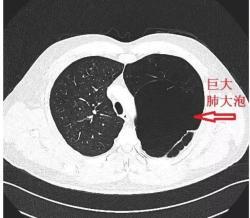

肺大泡 片子,肺大泡ct肺大疱

肺大泡ct肺大疱

肺大泡ct图片

肺大泡ct

肺大泡ct图解

肺大泡ct图片解读

肺大泡ct影像

肺大泡ct影像图片

肺大泡影像学表现图片

肺大泡在ct上的图像